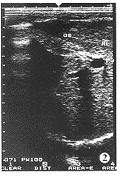

1.本研究所见胆囊大小基本在正常范围内,胆囊异常均有胆囊壁增厚、模糊、不光滑、回声增强,只是其程度有所不同。根据囊内回声不同将胆囊异常分为两型:Ⅰ型,囊内回声清晰(图1);Ⅱ型,囊内回声差,甚至不透声(图2)。

图1 Ⅰ型胆囊改变(GB-胆囊,RL-肝脏右叶)

图2 Ⅱ型胆囊改变(PV-门静脉)